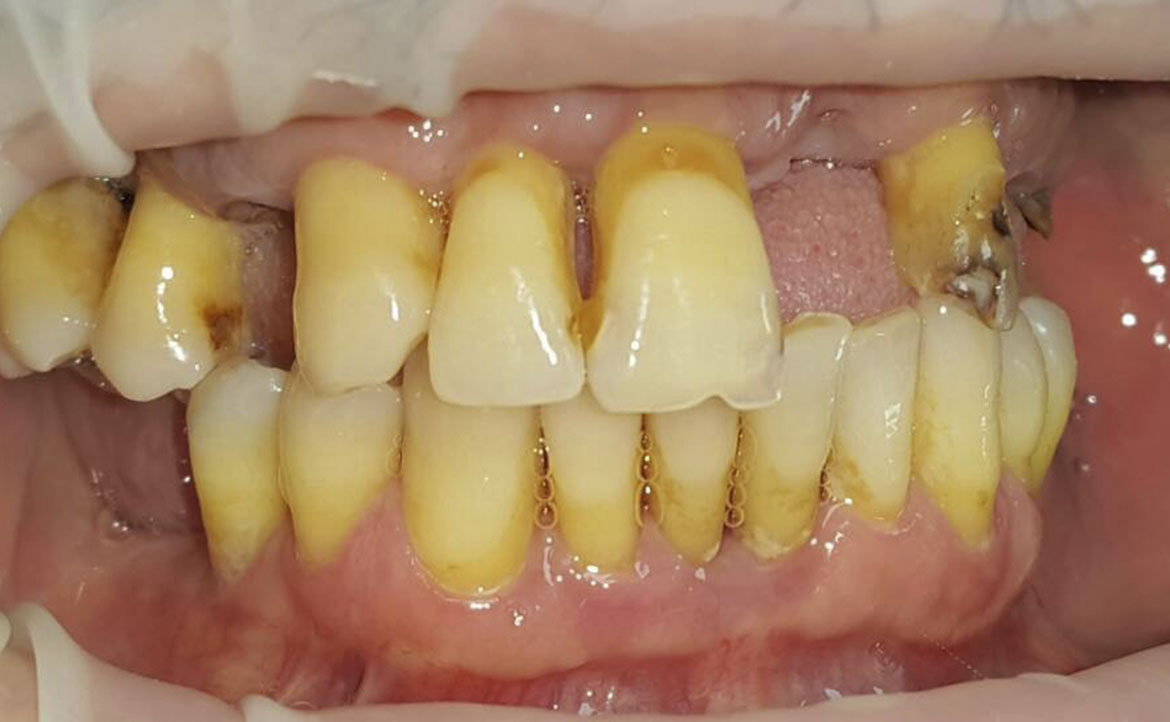

Sistemul Fast&Fixed este o alternativă imediată. Această procedură îți va permite să-ți recapeți zâmbetul și încrederea în sine într-un timp scurt. Deși rezultatul este imediat, durata de viață a acestui implant este pentru o perioadă îndelungată.

Este un sistem inovativ care permite o fixare rapidă și de lungă durată a dinților lipsă. În acest caz se folosește osul nativ al pacientului. În acest fel sunt eliminate alte intervenții adăugătoare, cum ar fi creșterea masei osoase. Acest sistem presupune doar câțiva pași: consultarea, elaborarea unui set de analize, amprentarea dentară, inserarea implanturilor provizorii, refacerea arcadelor dentare, iar la final fixarea danturii definitive. De la consultare până la obținerea unui zâmbet impecabil te despart doar 24 de ore.